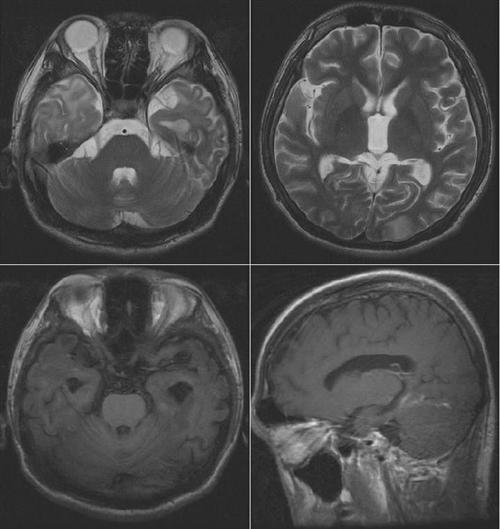

脑肺吸虫病是肺吸虫成虫寄生于脑内并不断移行造成的机械性损伤,及其代谢物等引起的免疫病理反应的一种疾病,以颞叶最常受损。脑肺吸虫病能治好吗?接下来跟大家分享下我的看法。

相关图片